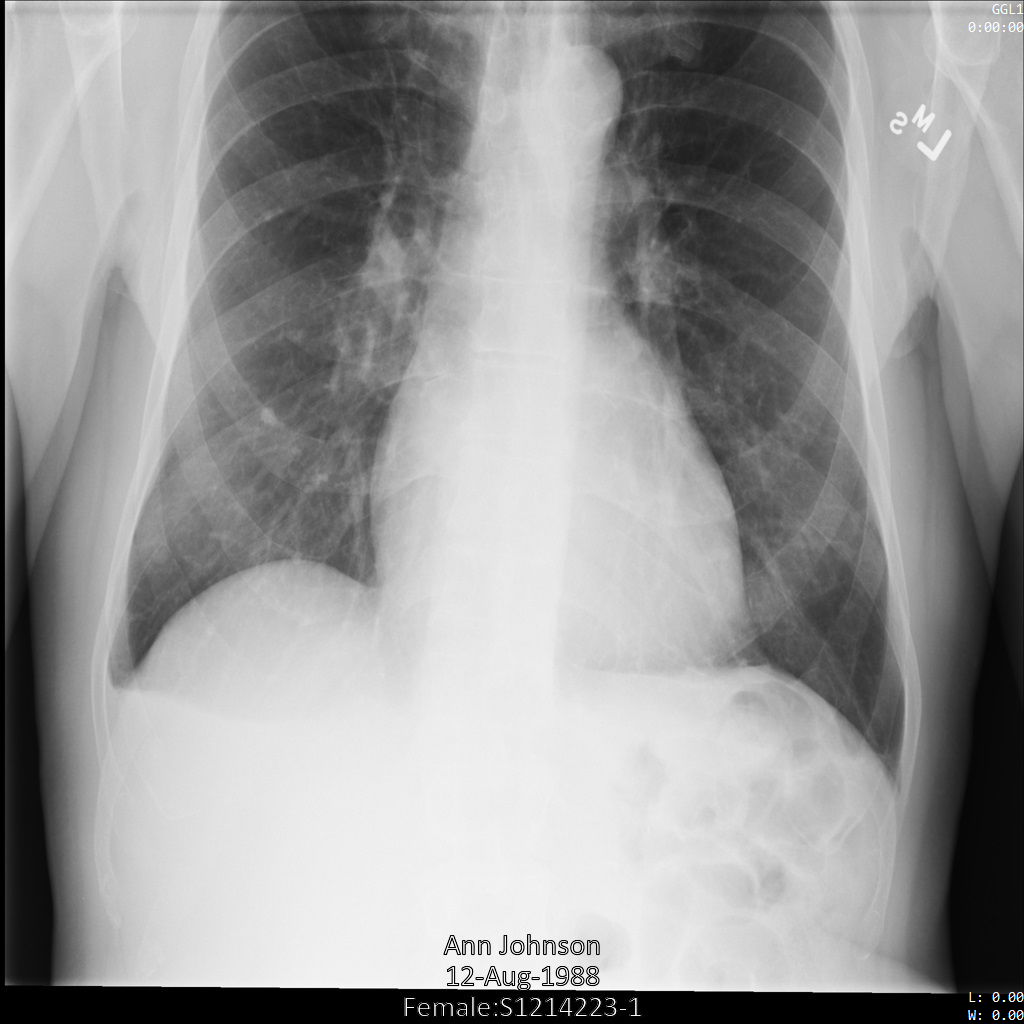

En los siguientes ejemplos, se muestra cómo desidentificar un conjunto de datos que contiene almacenes y datos de DICOM mediante el perfil de filtro de etiquetas ATTRIBUTE_CONFIDENTIALITY_BASIC_PROFILE.

Este perfil de filtro de etiquetas quita las etiquetas en función del Perfil básico de confidencialidad de atributos del Estándar de DICOM.

Después de enviar la imagen a la API de Cloud Healthcare mediante el perfil de filtro de etiqueta ATTRIBUTE_CONFIDENTIALITY_BASIC_PROFILE, la imagen aparece de la siguiente manera. Mientras se ocultan los metadatos que se muestran en las esquinas superiores de la imagen, permanece la PHI quemada que se encuentra en la parte inferior de la imagen.

Para quitar también el texto grabado, consulta Cómo ocultar el texto grabado de las imágenes.